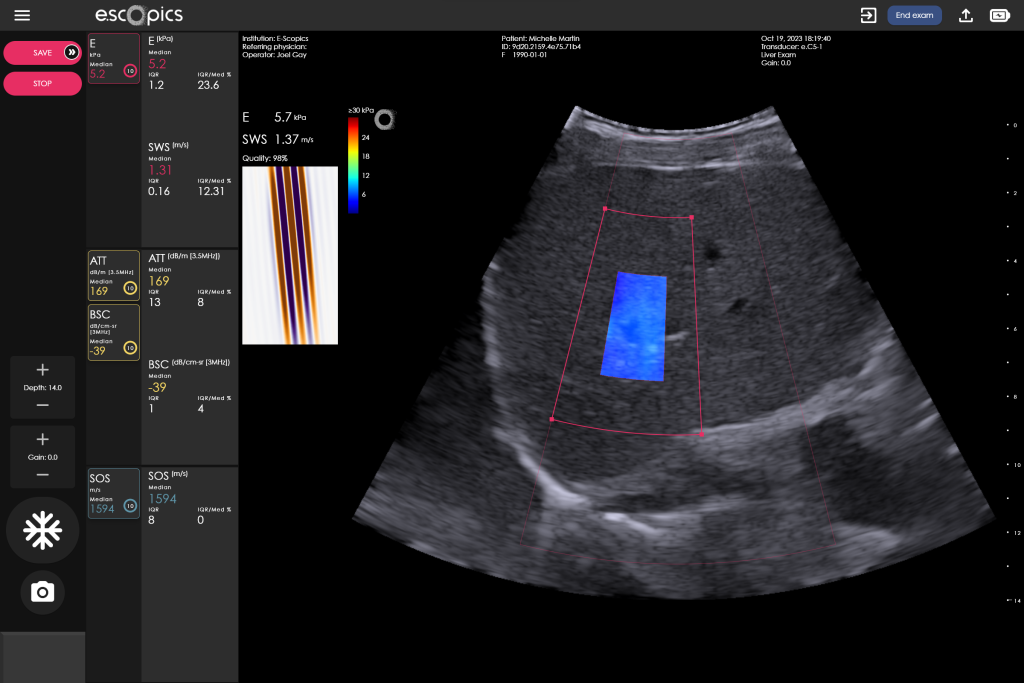

Quantitative Ultrasound

Measurements of liver brightness

3 parameters related to liver steatosis

Reproducible and repeatable quantitative measurements performed in real time, under image guidance

The Q.US Technology

Quantifying steatosis in the liver is the first step in the diagnosis of MASLD and primarily uses non-invasive ultrasound. Initially visual (qualitative), the assessment of fat in the liver has benefited from the development of quantitative ultrasound (QUS) which now offers objective measurements of steatosis-related parameters, surpassing subjective visual assessments.